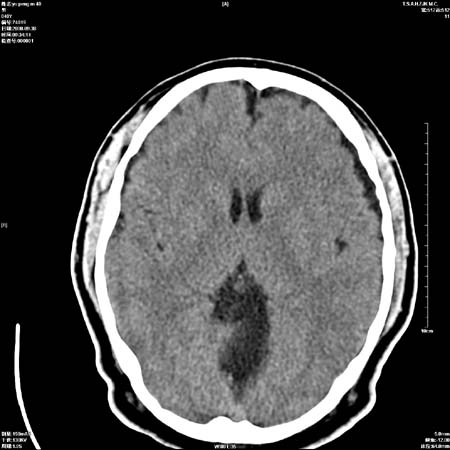

以下是引用zjzjr在2008-10-4 20:29:00的发言:[br]右颞叶皮质区密度略减低,脑沟较对侧变浅,考虑早期脑梗塞,建议mri.左侧小脑幕缘旁可见带状低密度影,轻度占位效应,支持蛛网膜囊肿,枕大池区亦考虑蛛网膜囊肿.

以下是引用zsl6918在2008-10-4 21:05:00的发言:[br]考虑蛛网膜囊肿

以下是引用一个人在2008-10-4 22:06:00的发言:[br]蛛网膜囊肿.

以下是引用杀毒软件在2008-10-4 21:51:00的发言:[br]支持考虑-----蛛网膜囊肿可能性大[br]